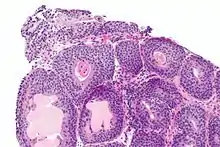

Histopathology of cystitis cystica.

Cystitis cystica is a relatively common chronic reactive inflammatory disorder thought to be caused by chronic irritation of the urothelium because of infection, calculi, outlet obstruction, or tumor resulting in multiple small filling defects in the bladder wall.[1]